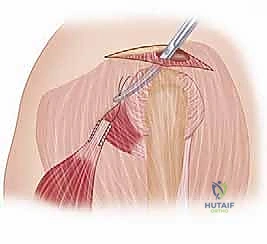

FIG 4 • A. Incision for latissimus dorsi transfer, extending from the posterior axillary fold to the posterior acromion.